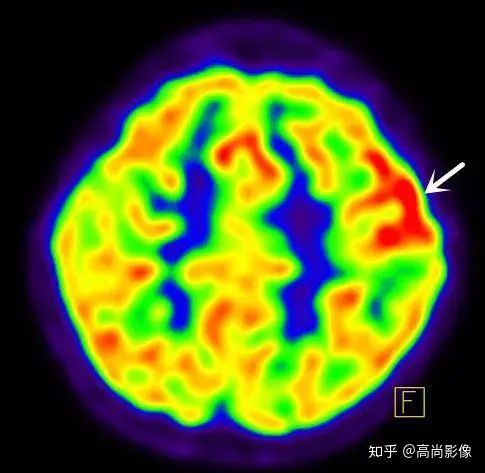

手抖?震顫?…還是帕金森?

多巴胺轉(zhuǎn)運體顯像可以幫助鑒別診斷帕金森和良性震顫,具有良好的診斷效能。

1年多來,黃大爺?shù)碾p手總是抖個不停,他和家人都非常擔(dān)心。黃大爺來到中心進(jìn)行了PET/CT的檢查,檢查發(fā)現(xiàn),黃大爺?shù)亩喟桶忿D(zhuǎn)運體顯像基本正常,最后,黃大爺被診斷為良性震顫。

雙側(cè)尾狀核、殼核多巴胺轉(zhuǎn)運體分布對稱、均勻

相比之下,童大媽就沒有這么幸運了。除了右邊身子總是抖動,童大媽還有嗅覺障礙、動作緩慢等癥狀。童大媽的PET/CT檢查結(jié)果符合帕金森的表現(xiàn),為臨床診斷提供了重要依據(jù)。

雙側(cè)尾狀核多巴胺轉(zhuǎn)運體分布對稱,左側(cè)殼核后部多巴胺轉(zhuǎn)運體分布較對側(cè)明顯減少,結(jié)合童大媽癥狀,先考慮帕金森。